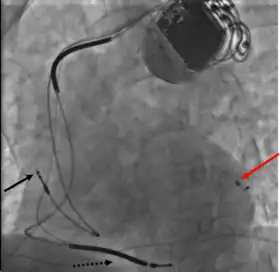

CRT devices have at least two leads, one passing through the vena cava and the right atrium into the right ventricle to stimulate the septum, and another passing through the vena cava and the right atrium and inserted through the coronary sinus to pace the epicardial wall of the left ventricle. Often, for patients in normal sinus rhythm, there is also a lead in the right atrium to facilitate synchrony with the atrial contraction. Thus, timing between the atrial and ventricular contractions, as well as between the septal and lateral walls of the left ventricle can be adjusted to achieve optimal cardiac function.

Biventricular pacing alone is referred to as CRT-P (for pacing). For selected patients at risk of arrhythmias, CRT can be combined with an implantable cardioverter-defibrillator (ICD): such devices, known as CRT-D (for defibrillation), also provide effective protection against life-threatening arrhythmias.[14]